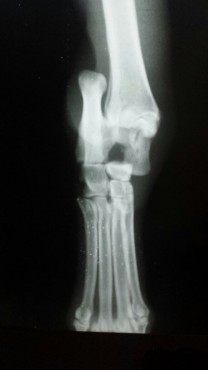

Casos Interessantes > ARTRODESE Tíbio-Tarsica por placa medial

Veja algumas Fotos